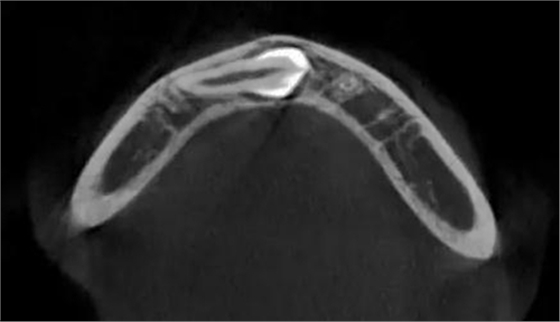

本案:患兒,女,14歲,因牙齒矯正來院,檢查見83滯留,43未見萌出,拍片發(fā)現(xiàn):43埋伏阻生于31、41、42根尖下方,按照正畸診療計劃,擬行43拔除術。

CBCT顯示